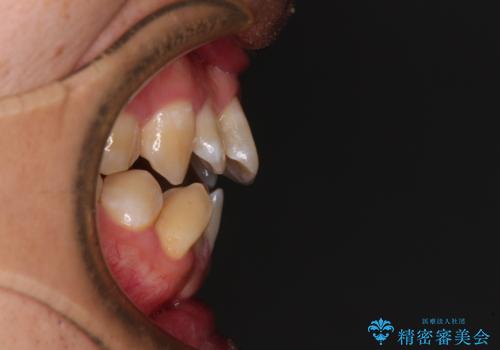

オープンバイトをインビザラインで矯正治療

- 前歯の開咬を気にして来院された患者様です。

開咬の治療は、前歯を閉じるように動かすとともに、上下臼歯を圧下(骨内にめり込ませる)させることで進めて行きます。

インビザラインは臼歯の圧下を効果的に行えるため、インビザラインを用いて矯正治療を行うこととしました。